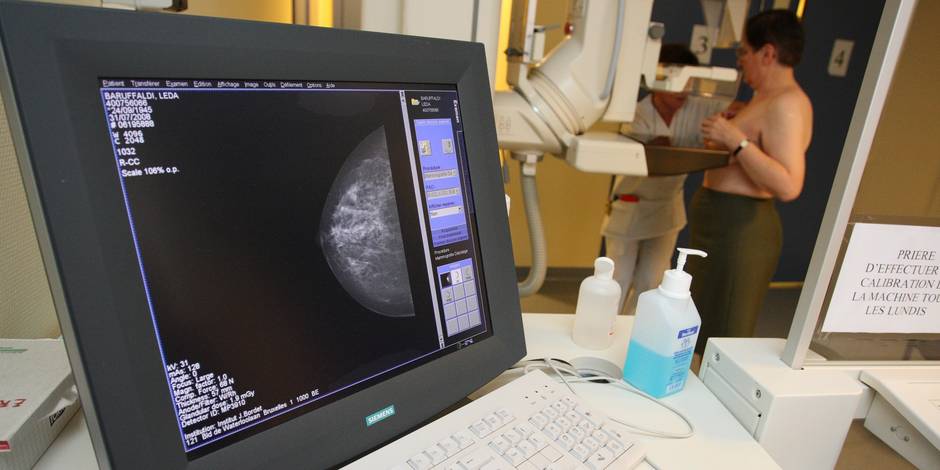

Améliorer le diagnostic du cancer du sein afin de trouver le traitement optimal et pouvoir prédire si la patiente répondra à la chimiothérapie: voilà ce que va permettre la découverte de chercheurs de la Faculté de Médecine de l'ULB et de l'Institut Jules Bordet, tous deux membres du Centre de Recherche de l’ULB sur le Cancer (U-CRC).

Les équipes du Pr. François Fuks (directeur du Laboratoire d’Epigénétique du Cancer à l’ULB) et le Dr. Christos Sotiriou (directeur du Laboratoire de Recherche Translationnelle du Cancer du Sein de l'Institut Jules Bordet) ont découvert une signature basée sur des changements de méthylation de l'ADN dans le cancer du sein, qui améliore le diagnostic en quantifiant les cellules immunitaires dans les tumeurs. En outre, non seulement cette signature prédit aussi, au moment du diagnostic de cancer du sein, si la patiente répondra à la chimiothérapie, mais en plus, elle améliore le diagnostic de nombreux autres cancers, y compris le mélanome et le cancer du poumon.

La majorité des patientes recevant aujourd'hui un traitement "par défaut", la demande pour un test visant à prédire l’efficacité de la chimiothérapie pour le cancer du sein est essentielle. Car un temps précieux peut être perdu si le traitement optimal n'est pas administré immédiatement après le diagnostic. Aussi, afin d'améliorer cette situation, Diagenode, une société wallonne basée à Liège et spécialisée dans les essais diagnostiques et les outils de recherche en épigénétique, s'est-elle associée aux laboratoires des Prs Fuks et Pr. Sotiriou pour développer un test basé sur cette nouvelle signature pour un usage en routine clinique. Ce test sera offert aux oncologues pour les aider à choisir le meilleur traitement pour leurs patientes.

Le cancer du sein est le cancer le plus fréquent chez les femmes en Belgique avec plus de 10.000 cas diagnostiqués chaque année. Une femme sur neuf en sera atteinte au cours de sa vie dans notre pays. Bien que les progrès majeurs dans le domaine des thérapies aient amélioré la survie des patientes, cette maladie demeure la principale cause de décès par cancer chez les femmes, en Belgique tout comme dans le reste du monde.